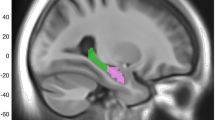

Aging is associated with reductions in hippocampal volume that are accelerated by Alzheimer's disease and vascular risk factors. Our genome-wide association study (GWAS) of dementia-free persons (n = 9,232) identified 46 SNPs at four loci with P values of <4.0 × 10−7. In two additional samples (n = 2,318), associations were replicated at 12q14 within MSRB3-WIF1 (discovery and replication; rs17178006; P = 5.3 × 10−11) and at 12q24 near HRK-FBXW8 (rs7294919; P = 2.9 × 10−11). Remaining associations included one SNP at 2q24 within DPP4 (rs6741949; P = 2.9 × 10−7) and nine SNPs at 9p33 within ASTN2 (rs7852872; P = 1.0 × 10−7); along with the chromosome 12 associations, these loci were also associated with hippocampal volume (P < 0.05) in a third younger, more heterogeneous sample (n = 7,794). The SNP in ASTN2 also showed suggestive association with decline in cognition in a largely independent sample (n = 1,563). These associations implicate genes related to apoptosis (HRK), development (WIF1), oxidative stress (MSR3B), ubiquitination (FBXW8) and neuronal migration (ASTN2), as well as enzymes targeted by new diabetes medications (DPP4), indicating new genetic influences on hippocampal size and possibly the risk of cognitive decline and dementia.